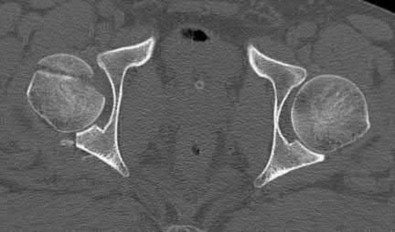

Question 4:

A 12-year-old obese male presents with a stable slipped capital femoral epiphysis (SCFE) of the left hip. Which of the following factors is the strongest indication for prophylactic in situ pinning of the asymptomatic contralateral right hip?

Options:

- Body Mass Index greater than the 95th percentile

- Slip angle greater than 50 degrees on the affected side

- Age greater than 14 years at presentation

- Presence of an underlying endocrine disorder (e.g., hypothyroidism)

- Male gender

Correct Answer: Presence of an underlying endocrine disorder (e.g., hypothyroidism)

Explanation:

Prophylactic pinning of the contralateral hip in SCFE is controversial but is strongly indicated in patients with a high risk of bilateral involvement. Risk factors predicting contralateral slip include an underlying endocrine disorder (such as hypothyroidism, panhypopituitarism, or renal osteodystrophy), prior radiation therapy, or age of presentation less than 10 years (or low modified Oxford bone age score).